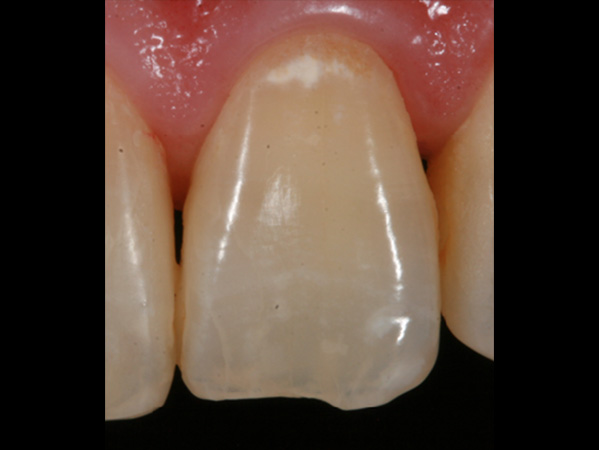

歯の表面に見られる白濁したシミのような斑点をホワイトスポットと呼びます。

初期う蝕はいわゆる穴のあいたう蝕の前段階のものです。歯の表面は溶けず、内側のミネラルなどが溶け出し空洞になることで光の屈折率が変わりホワイトスポットとして見た目に影響が出ます。

エナメル質形成不全ではう蝕とは異なり内部が空洞化することはありませんが、内部の構造が乱れることで光の屈折率が変わり、ホワイトスポットとして審美的に問題を生じます。